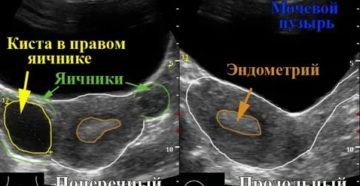

Можно ли перепутать кисту с беременностью: сравнение симптомов Современные методы диагностики позволяют довольно точно поставить…

Могут ли перепутать кисту с беременностью на УЗИ Патологическое образования на яичниках и беременность не…